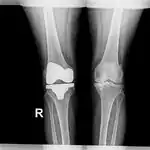

Diagnosis is made using medical imaging, often when investigating another problem.[3] Tests include X-ray, CT scan, Magnetic resonance imaging and Positron emission tomography.[1] The precise diagnosis is based on histology.[1]

Diagnosis includes medical imaging.[1] Distinguishing a large non-cancerous cartilage tumor, such as an enchondroma, from a chondrosarcoma grade I or atypical cartilaginous tumour is difficult.[6] Often, there are overlapping histological features.[7]